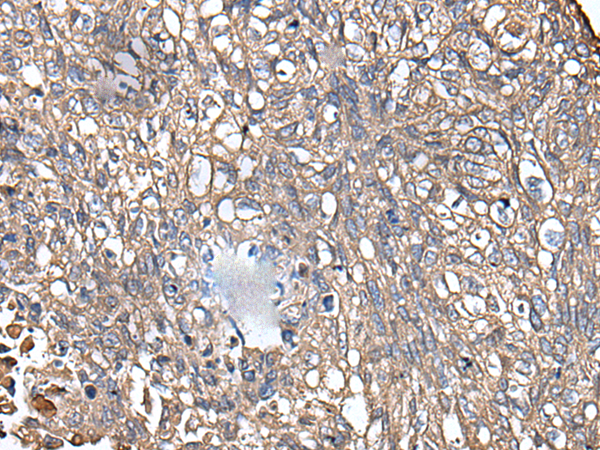

IHC positive control: |

Human prostate cancer and human lung cancer |

IHC Recommend dilution: |

40-200 |